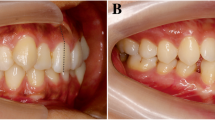

From among patients between the ages of 18 and 39 years who sought orthodontic treatment at the Tokyo Medical and Dental University Dental Hospital between 2012 and 2015, only those who required CBCT for diagnosis and treatment planning were selected. Written consent was obtained from all subjects after explanation of the research aims and goals.

The exclusion criteria were (1) history of orthodontic treatment, (2) missing or supernumerary maxillary incisors, 3) midline deviation of maxillary incisors ≥2 mm from the facial midline, (4) prosthodontic treatment of maxillary incisors, 5) evident nasopalatine pathology (e.g., nasopalatine duct cysts), (6) history of trauma to maxillary incisors, and 7) congenital anomalies (e.g., cleft lip and palate). Based on the inclusion and exclusion criteria, 93 subjects (male, 31; female, 62; mean age, 24.3 ± 5.6 years) were finally selected. Their skeletal pattern was Class I, Class II, and Class III and their mean ANB was 3.1 ± 3.5 (range −4.6–9.0).